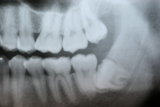

Wisdom Tooth Removal

Sometimes wisdom teeth are not functional, but instead create swelling and pain in the surrounding soft tissue, and they need to be taken out.

During the development of wisdom teeth, they often push away their neighboring teeth and contribute to anterior teeth crowding. Therefore, extraction of wisdom teeth is recommended in their early stage of eruption to prevent anterior crowding. The stress of eruption of wisdom teeth that grow horizontally causes dental decay on the 2nd molars and extraction is recommended before dental decay initiates.

Before / After